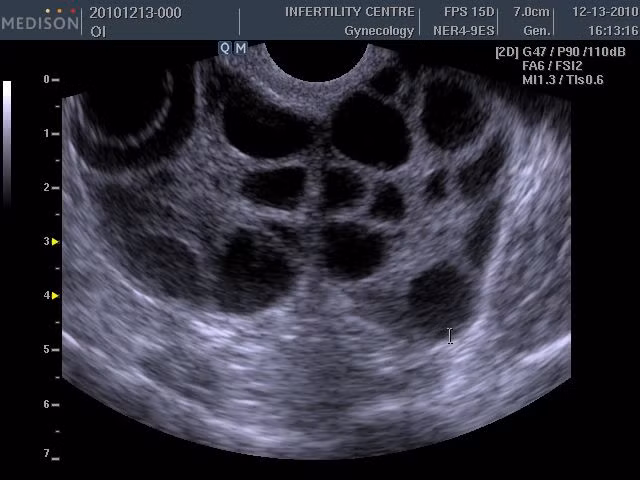

Các nhà nghiên cứu đã từng cảnh báo về nguy cơ nghẽn máu có thể ảnh hưởng tới tính mạng sau khi phụ nữ thụ tinh trong ống nghiệm. Nguy cơ bị đột quỵ ở sản phụ thụ tinh ống nghiệm cao gấp 5 lần sản phụ mang thai tự nhiên. Nguyên nhân là do lượng oestrogen tăng lên quá cao sau khi uống thuốc điều trị vô sinh. Thuốc này cũng khiến phụ nữ bị quá khích buồng trứng. (Nguồn ảnh: Liverpoolecho)